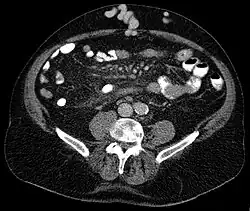

| Axial CT showing portosystemic collateral circulation via the umbilical vein: caput medusae in liver cirrhosis .jpeg) | |

Caput medusae is the appearance of distended and engorged superficial epigastric veins, which are seen radiating from the umbilicus across the abdomen. The name caput medusae (Latin for "head of Medusa") originates from the apparent similarity to Medusa's head, which had venomous snakes in place of hair. It is also a sign of portal hypertension.[1] When the portal vein, that transfers the blood from the gastrointestinal tract to the liver, is blocked, the blood volume increases in the peripheral blood vessels making them appear engorged.[2] It is caused by dilation of the paraumbilical veins, which carry oxygenated blood from mother to fetus in utero and normally close within one week of birth, becoming re-canalised due to portal hypertension caused by formation of scar tissue (fibrosis) in the liver. The appearance is due to cutaneous portosystemic collateral formation between distended and engorged paraumbilical veins that radiate from the umbilicus across the abdomen to join systemic veins.[3]

In Liver Cirrhosis, the paraumbilical veins open up to transfer portal venous blood into systemic circulation. It results in caput medusae.[5]